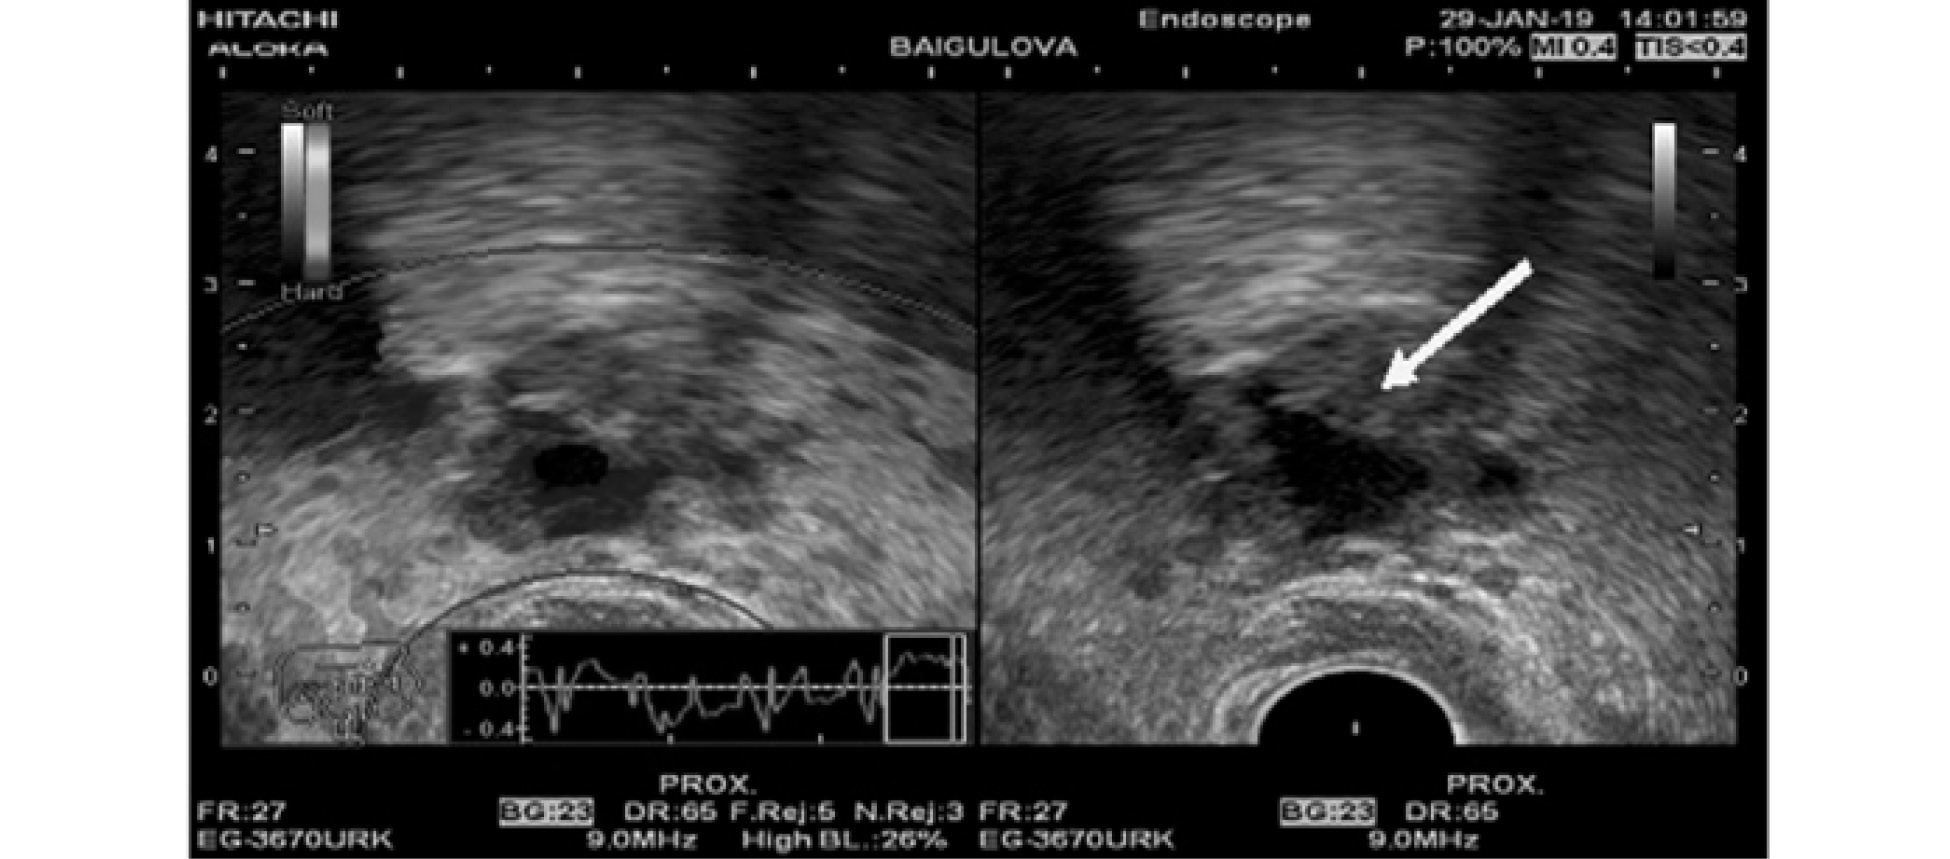

При эндоскопической ультрасонографии выявлены признаки папиллярной ткани в области кистозного образования ГПП. При помощи тонкоигольной пункции под ультрасонографическим контролем взят биопсионный и цитологический материал (рис. 4).

Рис. 4. Эндосонограмма. Признаки папиллярной ткани в области кистозного образования ГПП

По данным цитологического (cytospin, cell-block) исследования бесструктурные массы (детрит), эпителиальные клетки отсутствуют. При морфологическом исследовании верифицированы признаки внутрипротоковой папиллярной опухоли (Intraductal Papillary Mucinous Neoplasm — IPMN). Исследование онкомаркеров в аспированной кистозной жидкости показало повышение уровня СА 19-9 более 1000 нг/мл и СЕА более 27,2 нг/мл.